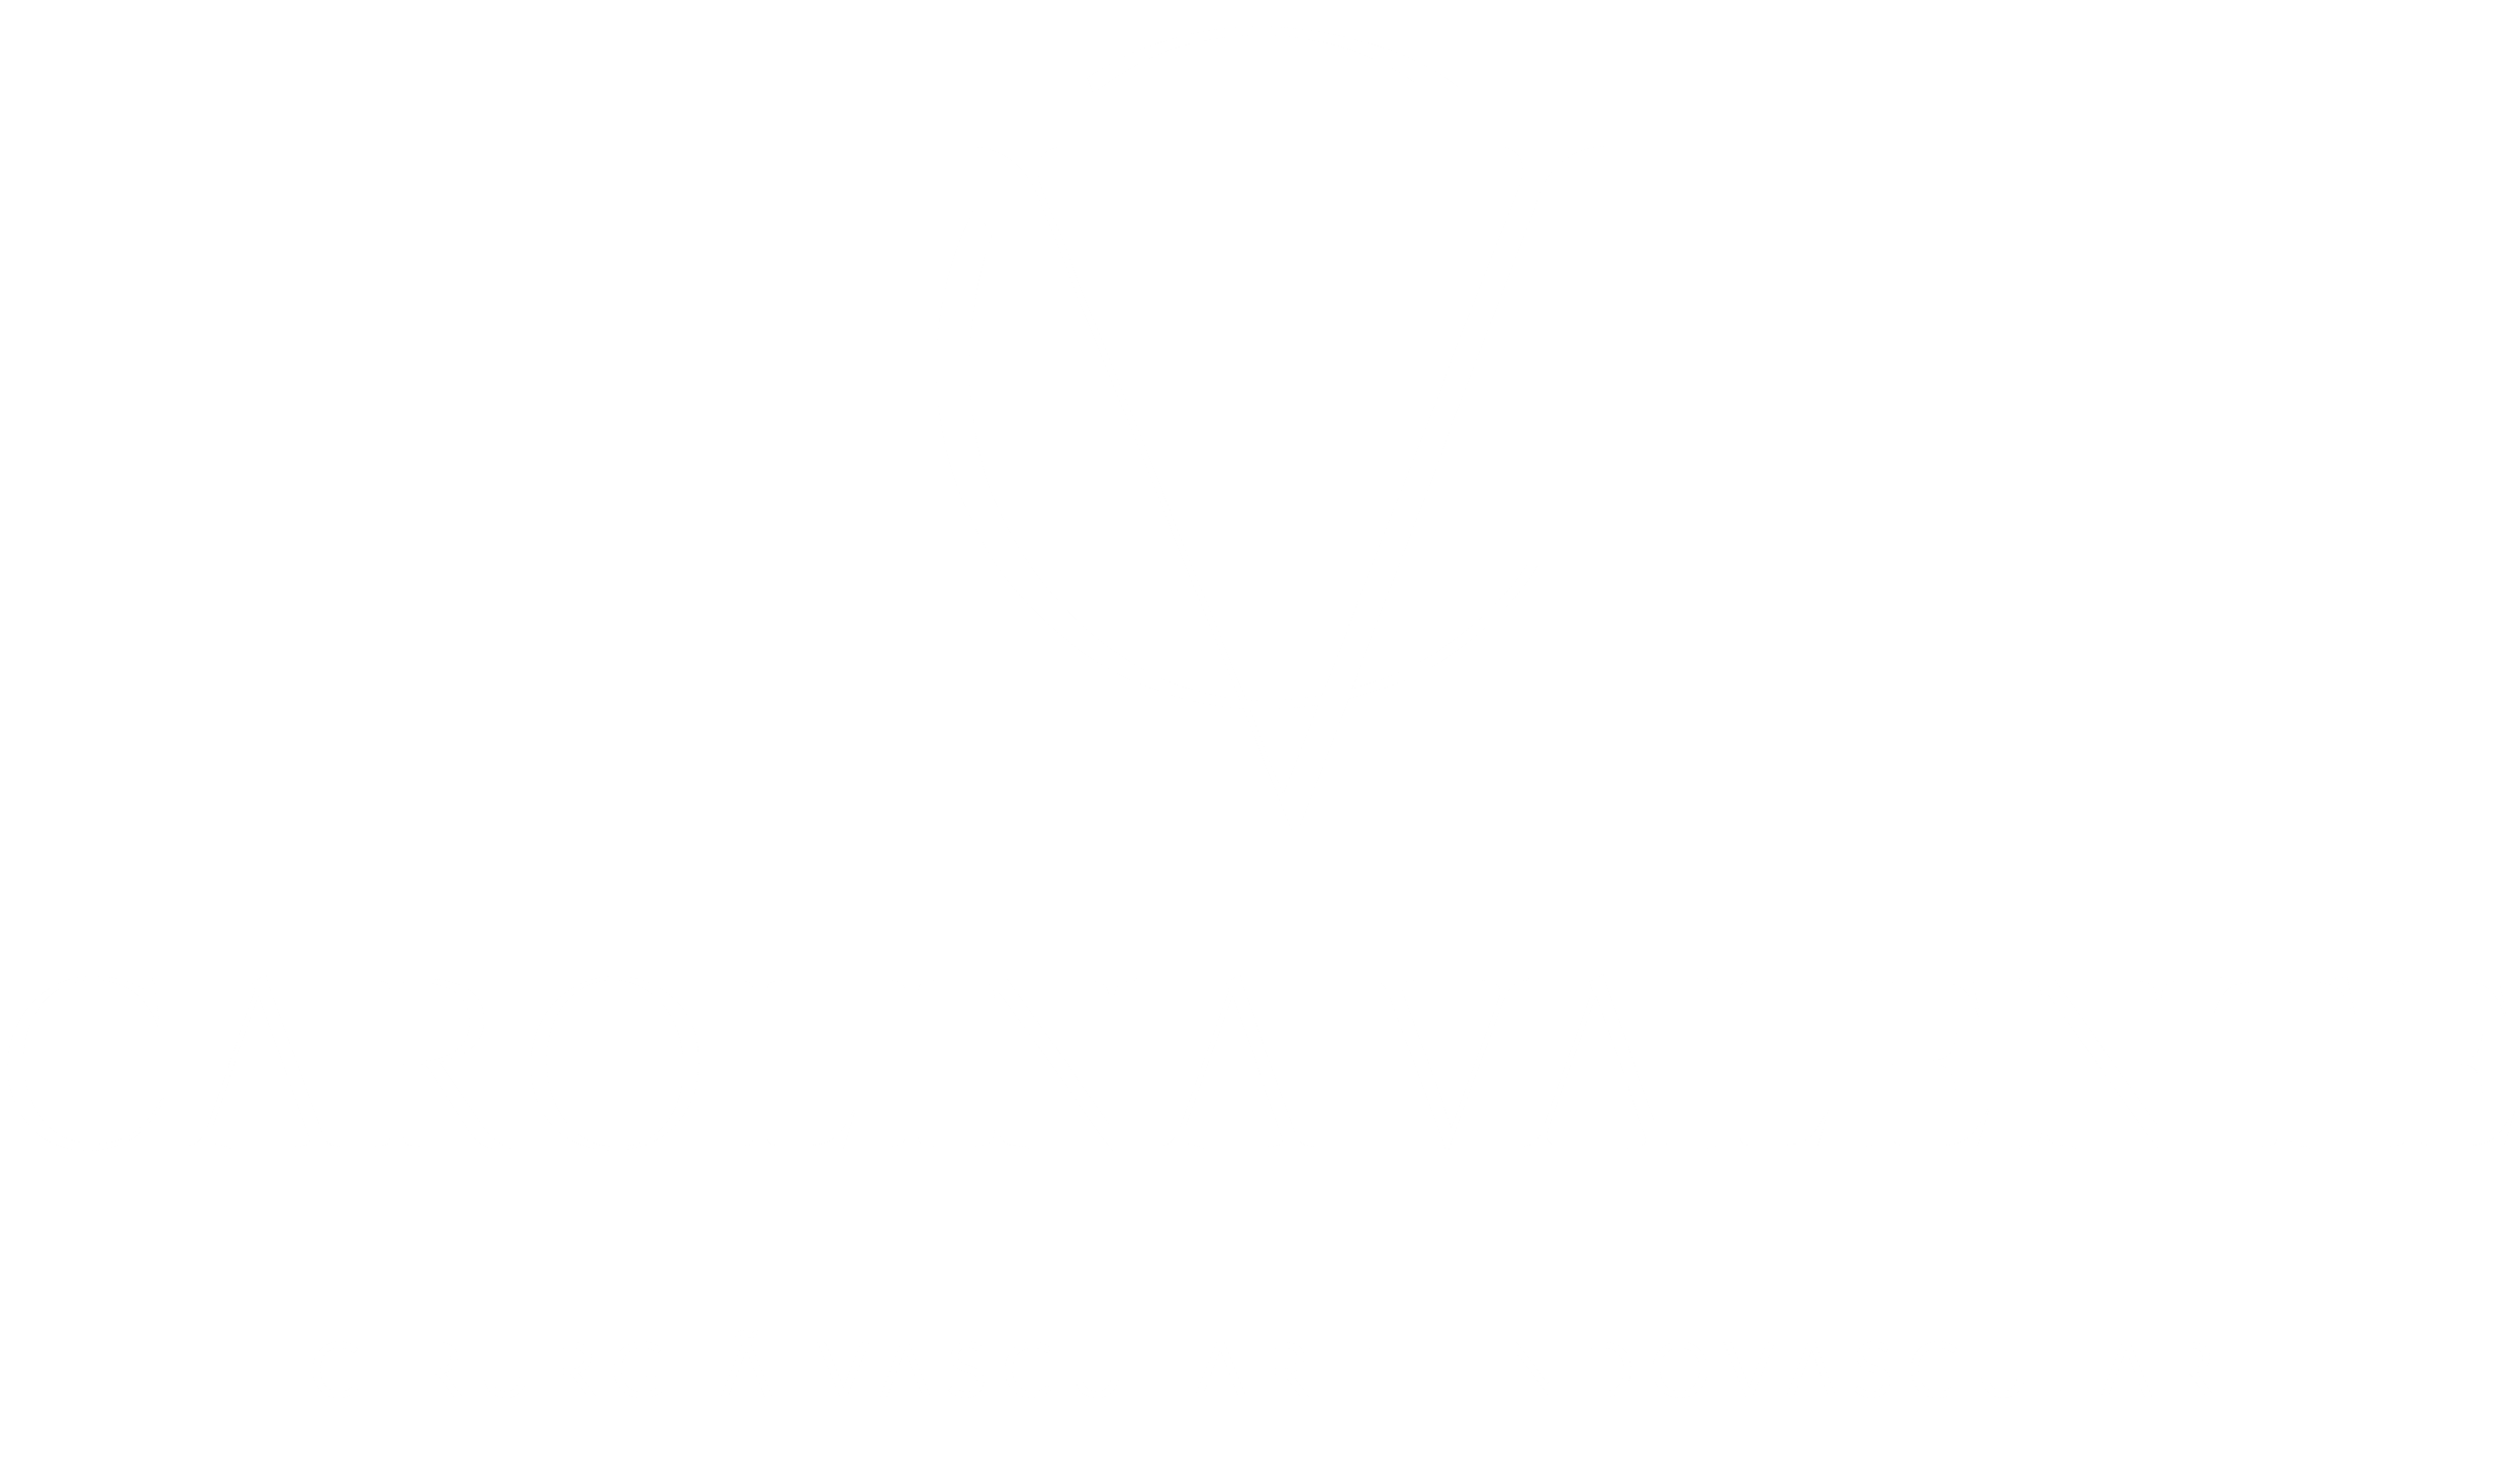

A base da técnica endovascular é a angiografia, que consiste em inserir um cateter dentro do vaso sanguíneo para visualizar por onde o sangue está passando e tratar o problema diretamente no local. Tratamento com o mesmo princípio e popularmente conhecido é o cateterismo cardíaco. O processo é o mesmo porém, no caso de doenças cardíacas e infartos esse tratamento é feito diretamente nos vasos do coração. O cirurgião vascular é responsável por este tratamento nos demais vasos do organismo.

Nos últimos anos os procedimentos endovasculares tiveram grande crescimento, tanto no tocante ao refinamento dos materiais e das técnicas existentes, quanto no desenvolvimento de novos procedimentos e instrumentos.

BRITTO, Carlos José de. Cirurgia Vascular, Cirurgia Endovascular e Angiologia. 3. ed. Rio de Janeiro: Revinter, 2014. Seção II, Capítulo 13 – Fundamentos e técnicas básicas.